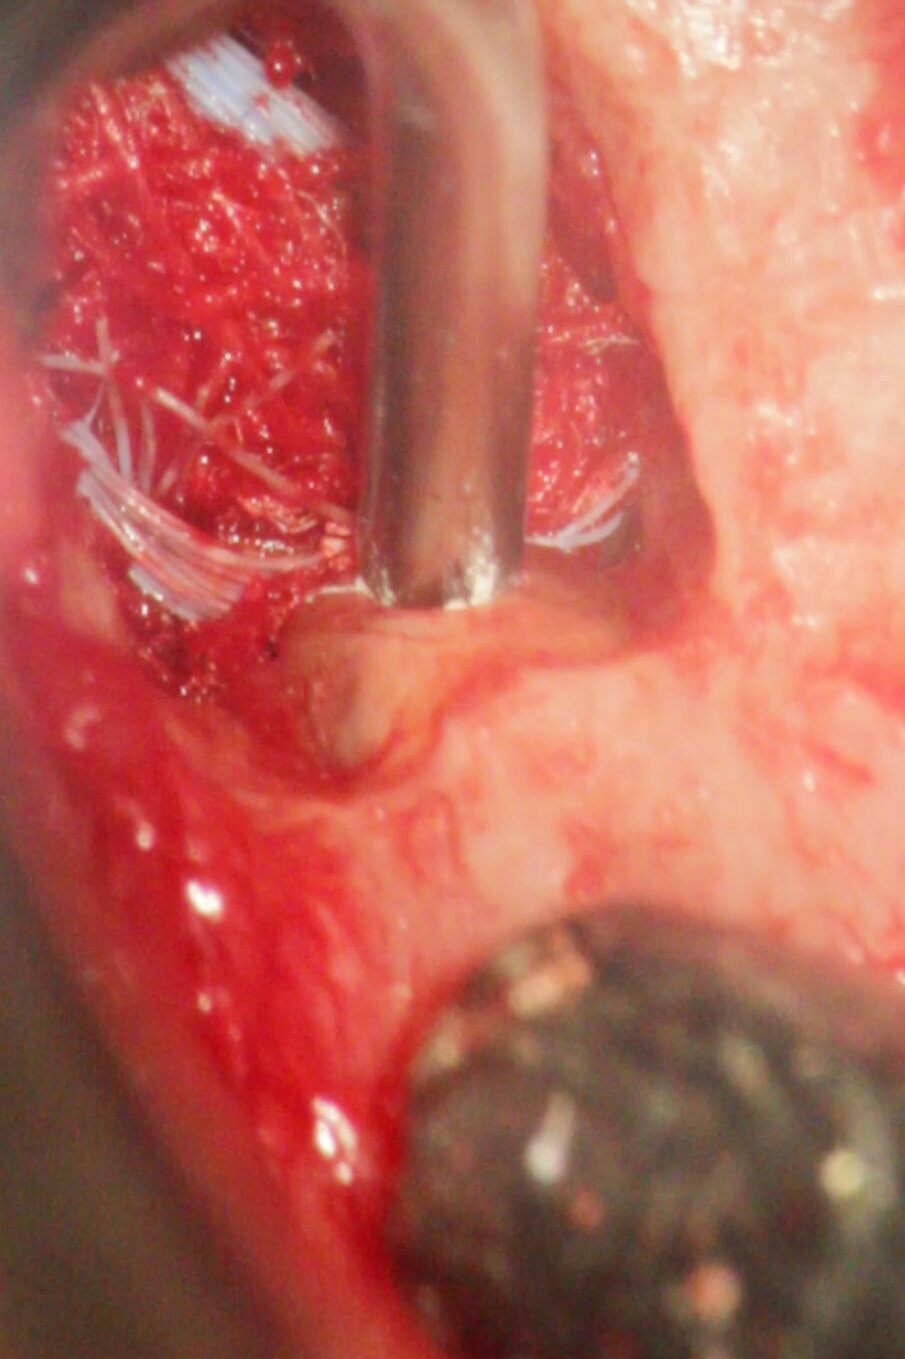

La perforazione accidentale della camera pulpare o del canale radicolare modifica in modo significativo la prognosi del dente. La riparazione della perforazione con un materiale sigillante biocompatibile come MTA può salvare i denti compromessi (Mente et al. 2014) (Figg. 3a-3e).

Riparazione delle perforazioni radicolari